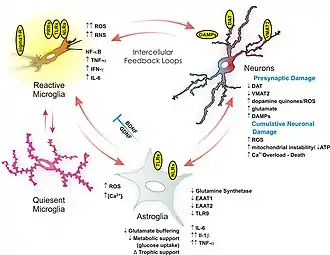

Neurotoxic and neuroimmunological

Methamphetamine is directly neurotoxic to dopaminergic neurons in both lab animals and humans.[27][28] Excitotoxicity, oxidative stress, metabolic compromise, UPS dysfunction, protein nitration, endoplasmic reticulum stress, p53 expression and other processes contributed to this neurotoxicity.[54][55][56] In line with its dopaminergic neurotoxicity, methamphetamine use is associated with a higher risk of Parkinson's disease.[57] In addition to its dopaminergic neurotoxicity, a review of evidence in humans indicated that high-dose methamphetamine use can also be neurotoxic to serotonergic neurons.[28] It has been demonstrated that a high core temperature is correlated with an increase in the neurotoxic effects of methamphetamine.[58] Withdrawal of methamphetamine in dependent persons may lead to post-acute withdrawal which persists months beyond the typical withdrawal period.[56]

Magnetic resonance imaging studies on human methamphetamine users have also found evidence of neurodegeneration, or adverse neuroplastic changes in brain structure and function.[28] In particular, methamphetamine appears to cause hyperintensity and hypertrophy of white matter, marked shrinkage of hippocampi, and reduced gray matter in the cingulate cortex, limbic cortex, and paralimbic cortex in recreational methamphetamine users.[28] Moreover, evidence suggests that adverse changes in the level of biomarkers of metabolic integrity and synthesis occur in recreational users, such as a reduction in N-acetylaspartate and creatine levels and elevated levels of choline and myoinositol.[28]

Methamphetamine has been shown to activate TAAR1 in human astrocytes and generate cAMP as a result.[57] Activation of astrocyte-localized TAAR1 appears to function as a mechanism by which methamphetamine attenuates membrane-bound EAAT2 (SLC1A2) levels and function in these cells.[57]

Methamphetamine binds to and activates both sigma receptor subtypes, σ1 and σ2, with micromolar affinity.[53][59] Sigma receptor activation may promote methamphetamine-induced neurotoxicity by facilitating hyperthermia, increasing dopamine synthesis and release, influencing microglial activation, and modulating apoptotic signaling cascades and the formation of reactive oxygen species.[53][59]

- ↑ Loftis JM, Janowsky A (2014). "Neuroimmune basis of methamphetamine toxicity". Neuroimmune Signaling in Drug Actions and Addictions. International Review of Neurobiology. Vol. 118. Academic Press. pp. 165–197. doi:10.1016/B978-0-12-801284-0.00007-5. ISBN 9780128012840. PMC 4418472. PMID 25175865.

Collectively, these pathological processes contribute to neurotoxicity (e.g., increased BBB permeability, inflammation, neuronal degeneration, cell death) and neuropsychiatric impairments (e.g., cognitive deficits, mood disorders)

"Figure 7.1: Neuroimmune mechanisms of methamphetamine-induced CNS toxicity Archived 16 September 2018 at the Wayback Machine" - 1 2 3 4 5 Kaushal N, Matsumoto RR (March 2011). "Role of sigma receptors in methamphetamine-induced neurotoxicity". Curr Neuropharmacol. 9 (1): 54–57. doi:10.2174/157015911795016930. PMC 3137201. PMID 21886562.